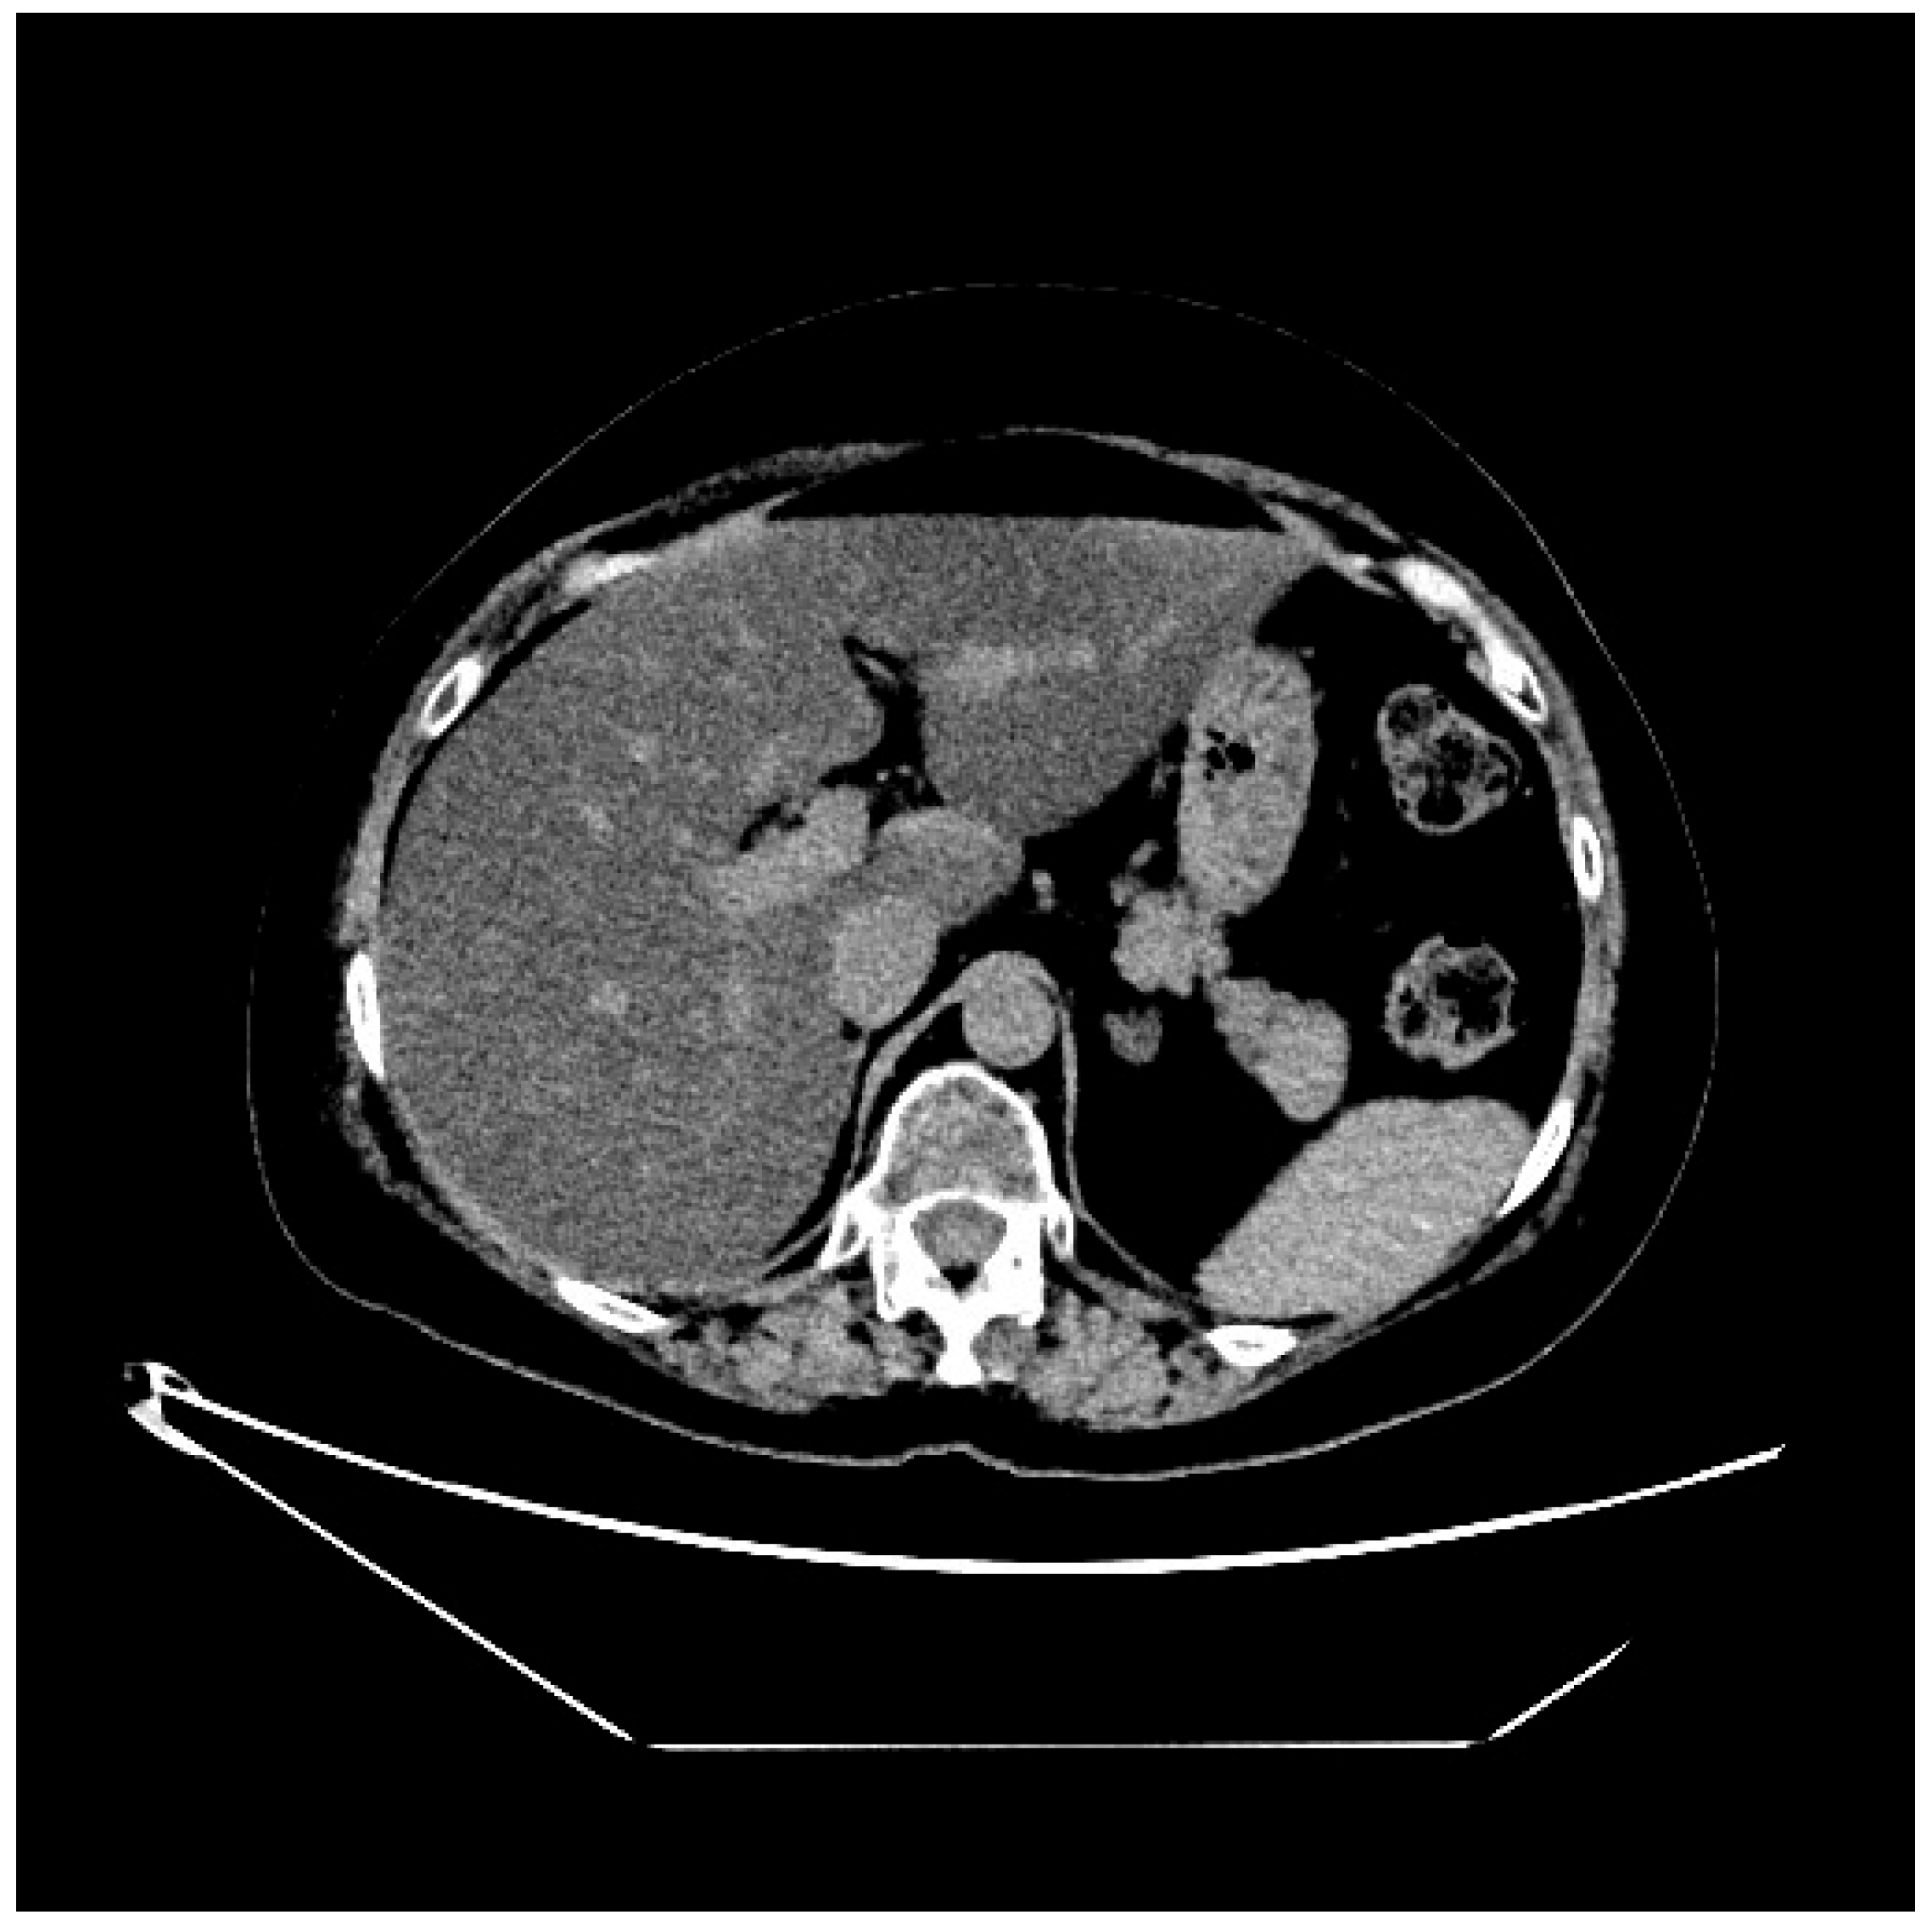

2. Case Presentation